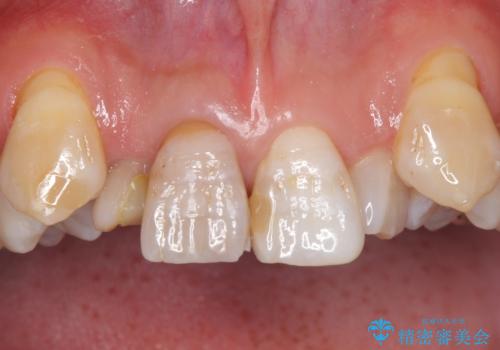

- 神経が死んでいる前歯2本(右上21)をセラミッククラウンでかぶせたいとご希望され、来院された患者様です。

歯並びにより、そのままだときれいに被せ物をいれられない状態でした。

補綴前矯正としてマウスピース矯正(インビザライン)を行った後、セラミッククラウンによる補綴治療を行いました。